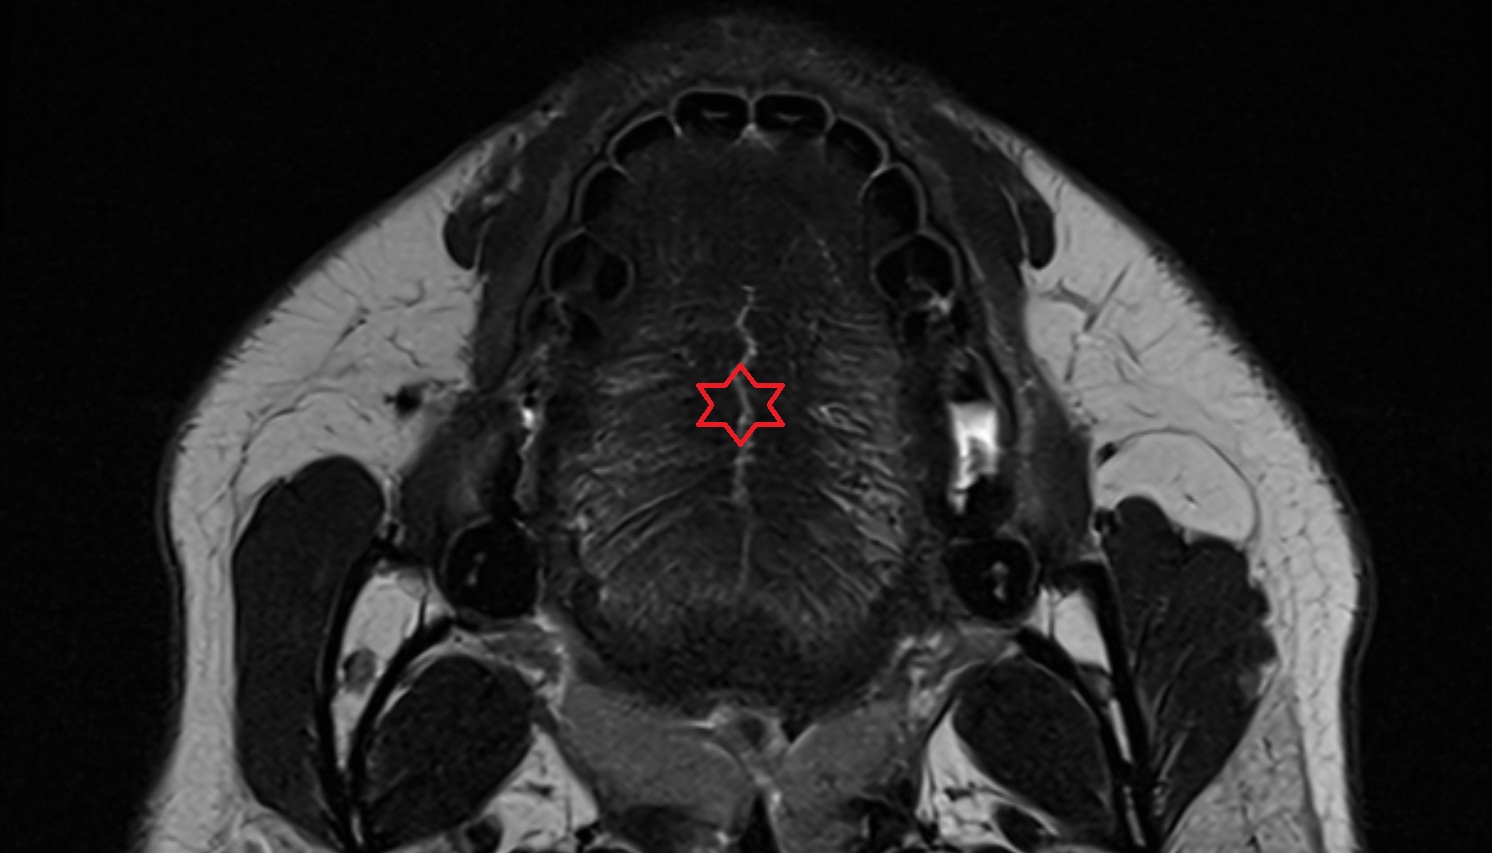

- Peripheral zone of prostate

- Anterior Fibromuscular Stroma of prostate

- Central zone of prostate

- Transitional zone of prostate